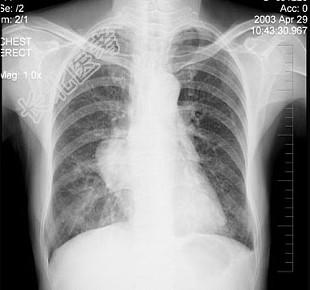

- 单项选择题女性,57岁, 因胸痛,咳嗽1个月就诊, 不发热,咳白色痰, 无痰中带血,X线检查见图, 最可能的诊断是 ( )

D、右肺肿瘤